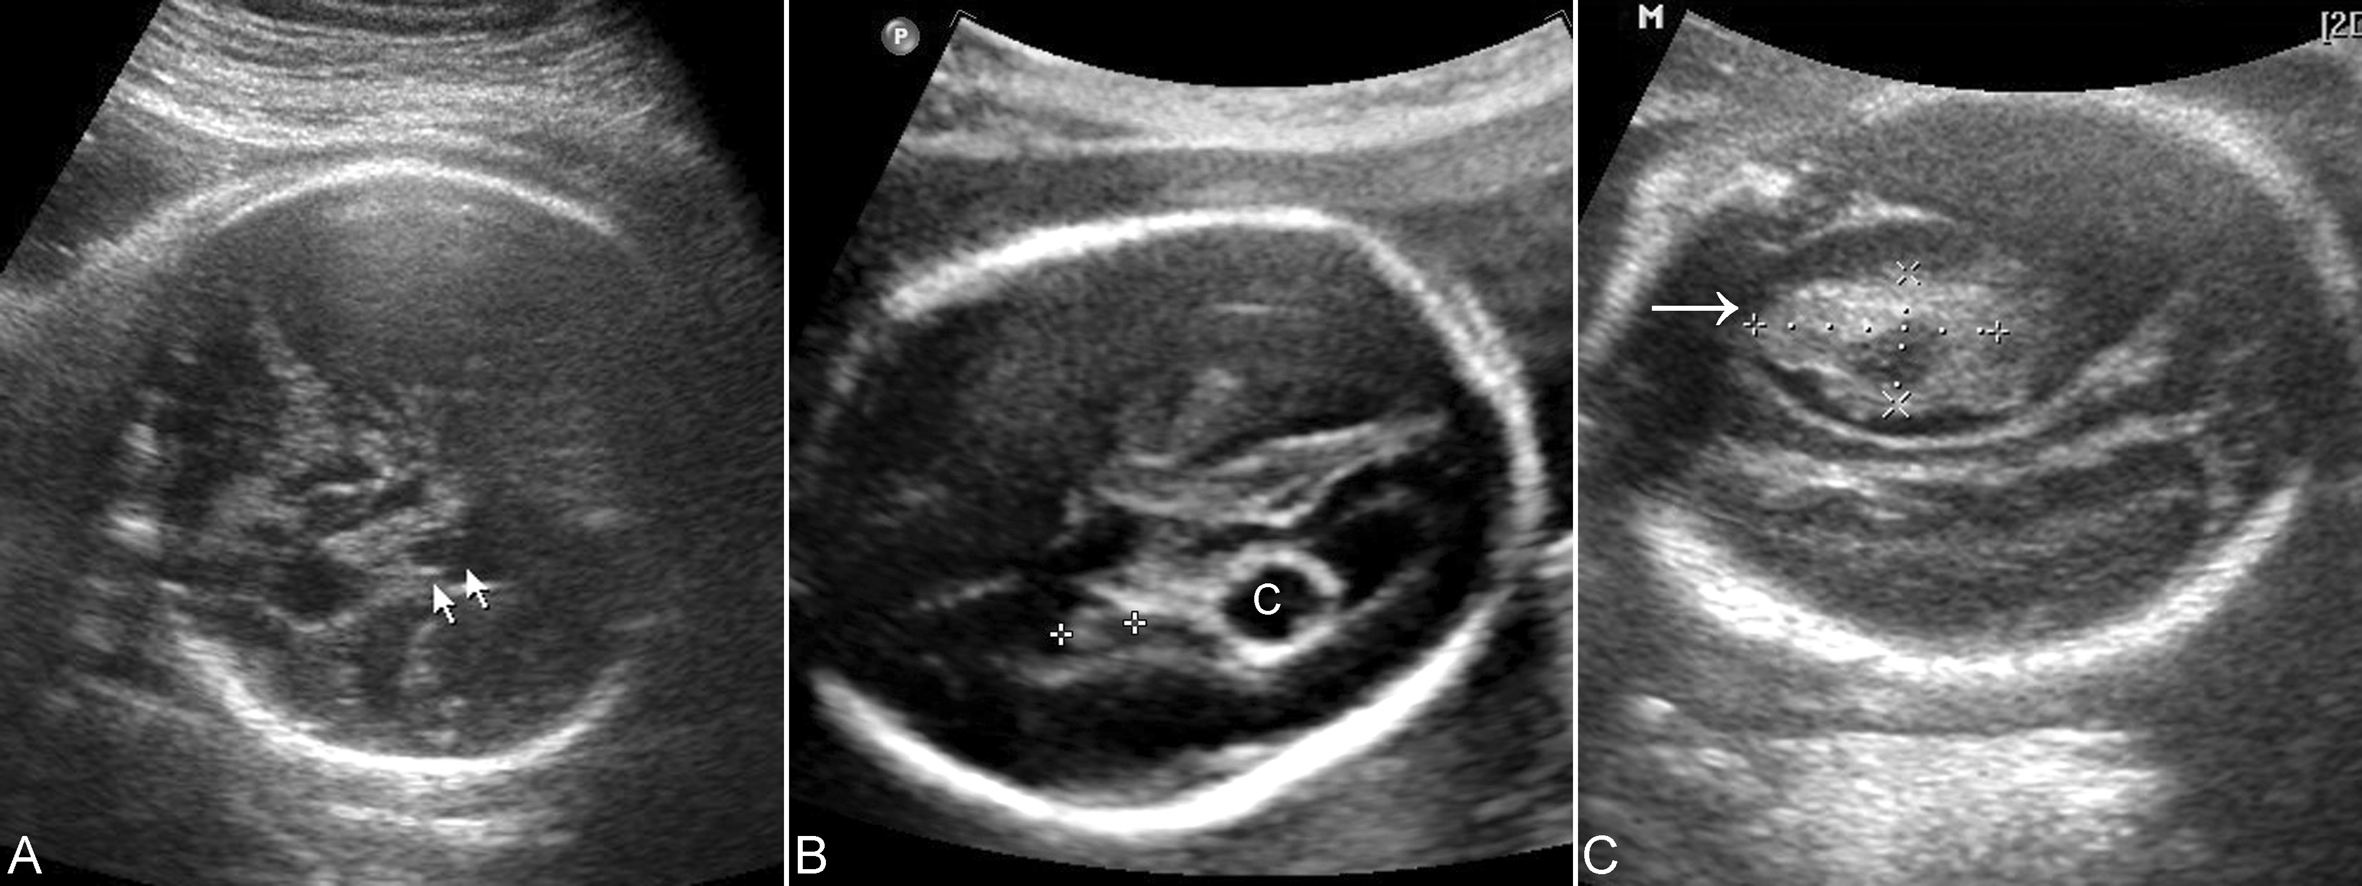

不同出血部位、出血量及不同出血阶段,颅内出血的声像图表现有很大差异。颅内出血1周内,出血区呈高回声,回声均匀; 出血1~2周后,出血区部分液化吸收呈不均匀混合性回声,边缘回声增强,内部可呈低回声或无回声; 出血 1个月后,出血区完全液化呈囊性无回声区(图3),有时可见不规则条索样强回声,为出血吸收后残存机化的纤维状物; 出血3个月后,出血量少的区域血块可消失或机化,脑部结构恢复正常。

根据出血部位不同,可以将出血分为幕上出血、幕下出血和硬膜下出血;根据出血程度不同,可以将出血分为四级:仅限于室管膜下基质的出血为Ⅰ级,Ⅱ级出血系指明确的脑室内出血,范围≤50%(一侧侧脑室),无脑室扩张(侧脑室宽度<15mm);脑室内出血范围>50%(一侧侧脑室)或累及两侧侧脑室、伴脑室扩张(侧脑室宽度≥15mm)时为Ⅲ级;最严重的Ⅳ级出血为Ⅰ~Ⅲ级颅内出血伴脑室周围实质内大范围出血(图3)。

图18-41胎儿颅内出血声像图